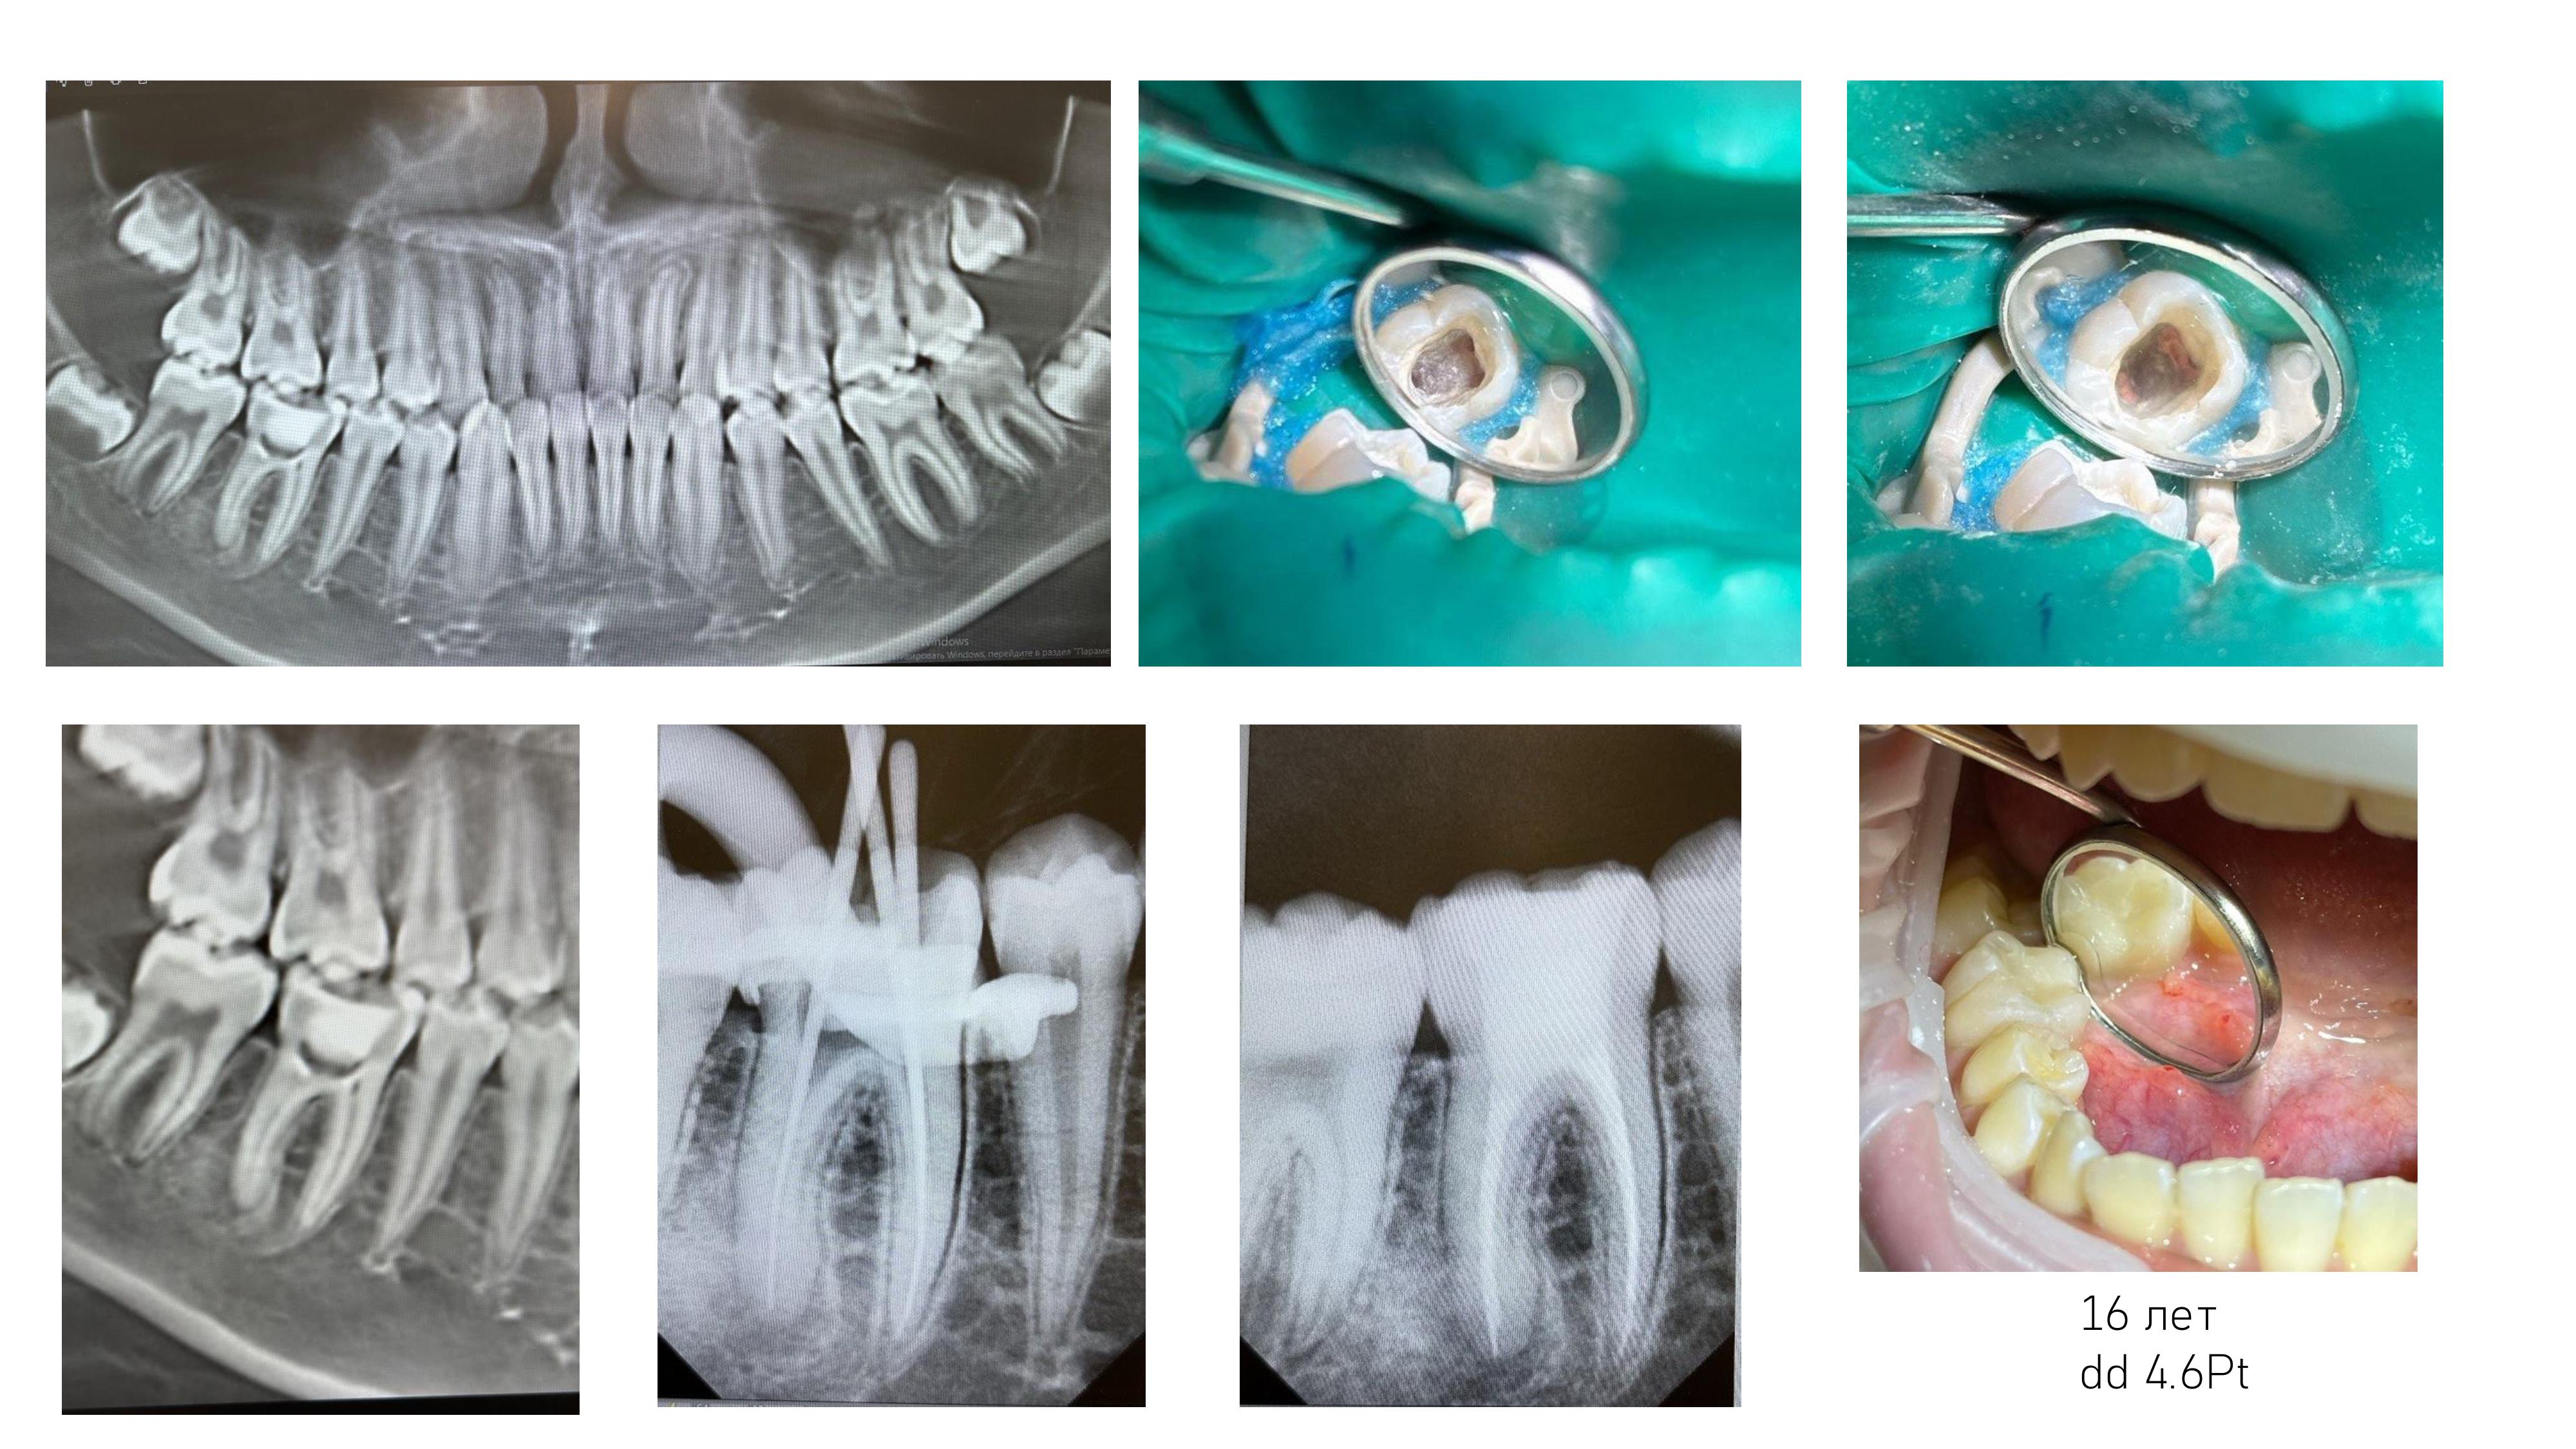

6. Диагностика и лечение кариеса временных и постоянных зубов с использованием микроскопа, лечение пульпитов и периодонтитов временных и постоянных зубов.

7. Подготовка зубов к ортопедическому и ортодонтическому лечению, с учетом назначенного плана лечения